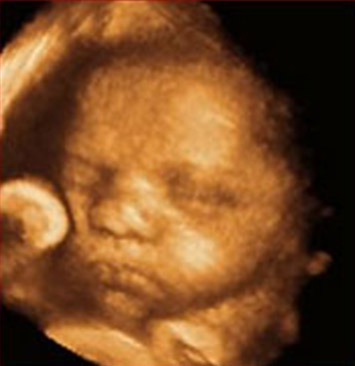

Laser treatment reduces risk of disability in affected twin fetuses.